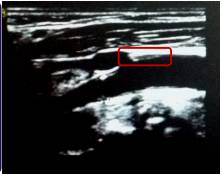

5、外周血管彩超

方框中为右侧颈总动脉

方框中为右侧颈内动脉起始部

●右侧颈总动脉中段前壁可见约16×2.0mm的强回声斑块。

●右侧颈内动脉起始部后壁可见约2.5×0.9mm的点状强回声。

●左侧颈总动脉中段前壁可见约17×1.7mm的不均质低回声斑块,近分叉处前壁、内侧壁、后壁可见偏心性不均质低回声斑块,致颈总动脉分叉处狭窄,直径狭窄率约50%。

●双侧颈总、颈内、颈外动脉粥样硬化斑块形成。

●左侧颈总动脉局部轻-中度狭窄。

●双侧髂、股、腘动脉粥样硬化斑点形成,双侧髂、股、腘静脉瓣无异常。